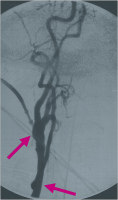

MR-Angiographie

Abbildung 1: Präoperative MR-Angiographie: Verschluss des Truncus brachiocephalicus (grüner Pfeil) und der linken Art. carotis communis und interna, hochgradige Abgangsstenose der linken Art. vertebralis (grüner Pfeil).